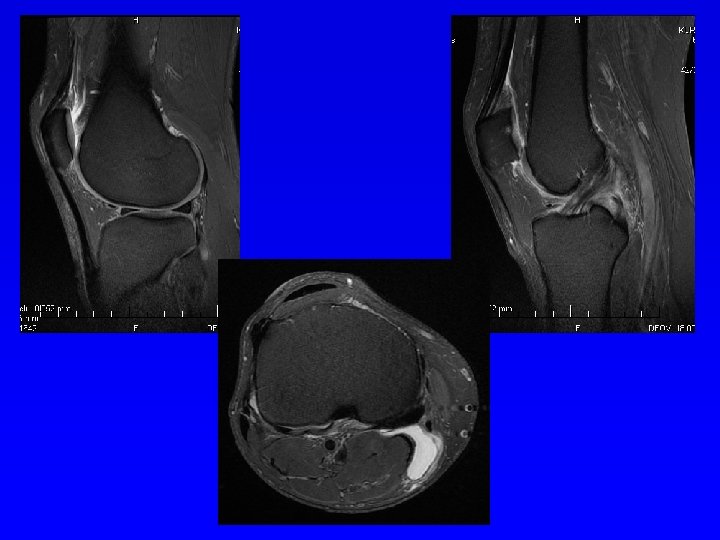

Magnetická rezonance MRI Silné magnetické pole Změny magnetických momentů spinu atomových jader s lichým atomovým číslem. Hyposignální- tmavé Hypersignální - světlé Nádory měkkých tkáně Onemocnění měkkých tkání Onemocnění páteře

MRI